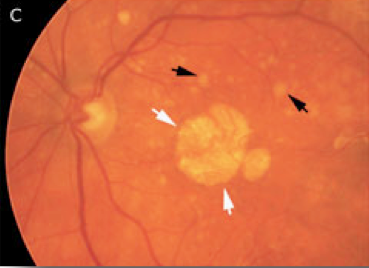

Con l’invecchiamento compaiono a livello della macula lesioni caratteristiche denominate drusen, che all’esame del fondo oculare appaiono come chiazzette bianco-giallastre. Sono accumuli di detriti cellulari non smaltiti come avviene normalmente, che si depositano al di sotto della retina (la presenza di queste lesioni rimane asintomatica). Col tempo l’accumularsi delle drusen può causare un danno dei fotorecettori della (la macula appare “secca”-“atrofica”) con conseguente riduzione della visione centrale più o meno grave. L’atrofia maculare è responsabile del 20% dei casi di cecità legale da degenerazione maculare senile.

A sinistra: macula sana. Al centro: drusen confluenti (frecce nere). A destra: forma secca della degenerazione maculare senile con atrofia della macula (frecce bianche) e drusen (frecce nere)